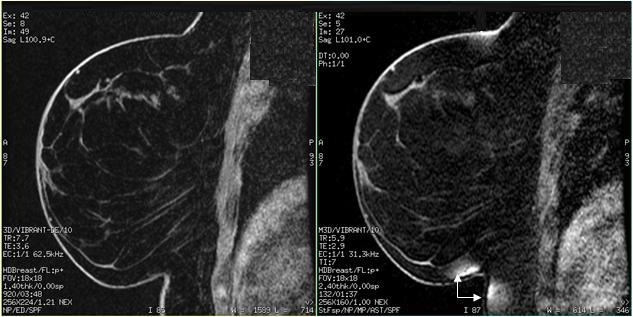

VIBRANT with Flex Imaging Option

VIBRANT (Volume Imaging for BReast AssessmeNT) with Flex Imaging Option is a single slab 3D, dual echo, Fast SPGR application that acquires out-of-phase and in-phase echoes used to generate fat and water images using a two-point Dixon technique. The VIBRANT with Flex is compatible with Breast coils and can be used for either bilateral or unilateral breast imaging.

To shorten scan time, VIBRANT with Flex uses a partial fourier acquisition technique and ARC. It also uses a high receive bandwidth to minimize chemical shift effects and to acquire the first out-of-phase and in-phase echoes within the same TR.